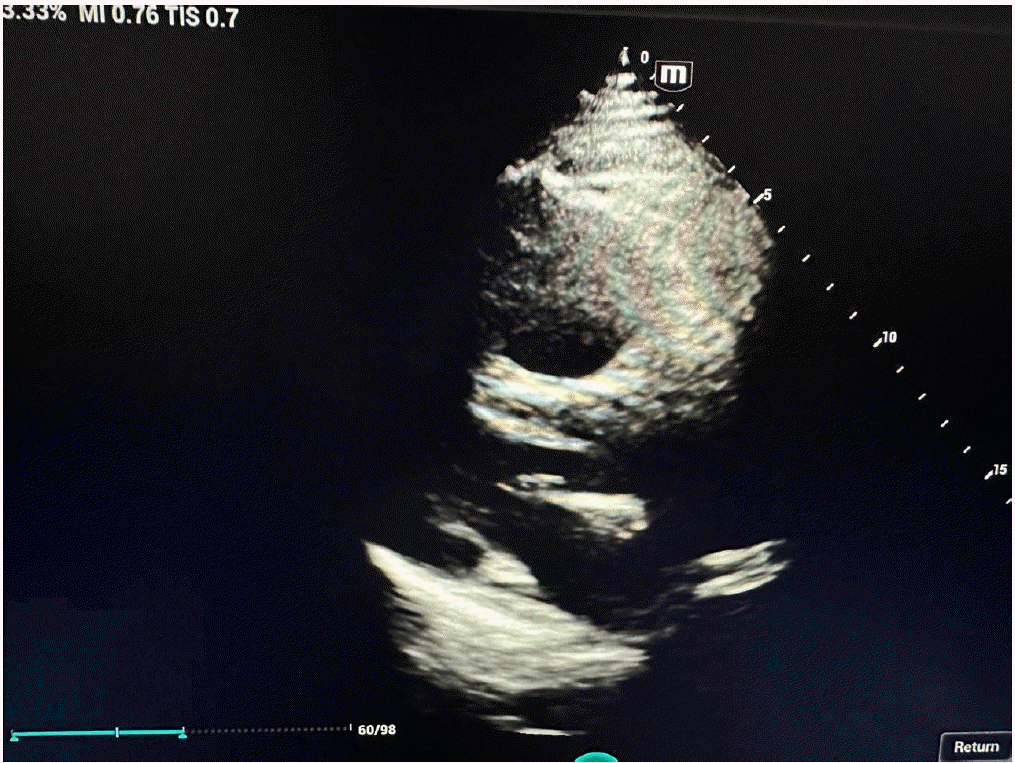

In view of severe respiratory distress and worsening hemodynamic status, he was intubated, and vasopressor commenced after fluid resuscitation. Computed tomography brain, chest and abdomen without contrast were done in view of high creatinine which revealed hemorrhagic brain contusion in the right posterior parietal and left higher parietal lobes. Two-dimensional echocardiography revealed severely dilated right atrium and right ventricle, jerky inter-ventricular septum with shift toward left ventricle, severe right ventricular dysfunction, and normal left ventricular systolic function (Figures 1-3). The lower extremity venous doppler showed evidence suggestive of thrombosis in bilateral superior femoral veins and left popliteal vein. Arterial blood gas analysis revealed nearly compensated metabolic acidosis with high lactate and hyperglycemia. On admission, lab include D-dimer of >20,000 ng/ml, serum creatinine 2.3 mg/dl, white blood cell counts 13,600 per microliter with normal hemoglobin and platelets counts, prothrombin time (PT) 23.1 seconds, international normalized ratio 1.7, and activated partial thromboplastin time (aPTT) 59.5 seconds. Liver function test revealed mildly elevated alanine transaminase and aspartate transferase (161 and 137 unit, respectively).